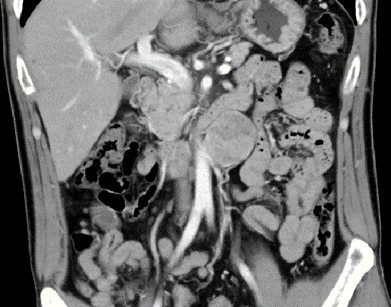

l CT:腹膜后腹主动脉旁软组织密度肿块,边界清,约4.2*4.3cm,密度不均,增强扫描皮髓质不均匀强化,实质期强化稍低,排泌期进一步减低。左肾2.0*2.3cm囊状低密度影。结论:左侧腹膜后占位,副神经节瘤?,左肾囊肿

6、 肾门下方、输尿管内侧和腹主动脉旁探及本次腹膜后肿物,目测尺寸5*5.5cm。复习CT可见肿瘤与腹主动脉关系密切,明显增强提示其血供丰富。术前阅片发现,肠系膜上动脉主干因肿瘤推挤向左侧移位。完整剥离减少出血是本次手术的重难点。且周围靠近十二指肠,操作中注意保护。

本例诊断为副神经节瘤,其与肾上腺内嗜铬细胞瘤同来源于神经节组织,位于交感神经旁,腹膜后主动脉和下腔静脉旁较多见。副神经节瘤为功能性神经内分泌肿瘤,好发于30~50岁,占腹膜后肿瘤的1%~3%,多位于肾动脉至腹主动脉分叉水平的主动脉旁区域。副神经节瘤为富血供肿瘤,增强后明显强化,动脉期显著,可有多支血管同时供应,肿块周围或实性成分内可见迂曲增粗的肿瘤血管,提示完整切除肿瘤、同时避免出血为手术团队提出了很大挑战。